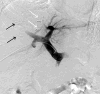

Background: Preoperative portal vein embolization (PVE) is increasingly used as a preparation for major hepatectomy in patients with inadequate liver remnant volume or function. However, whether segment 4 (S4) portal veins should be embolized is controversial. The effect of S4 PVE on the volume gain of segments 2 and 3 (S2+3) was examined.

Methods: Among 73 patients with uninjured liver who underwent right portal vein embolization (RPVE, n = 15) or RPVE extended to S4 portal veins (RPVE+4, n = 58), volume changes in S2+3 and S4 after embolization were compared. Clinical outcomes and PVE complications were assessed.

Results: After a median of 27 days, the S2+3 volume increased significantly after both RPVE and RPVE+4, but the absolute increase was significantly higher for RPVE+4 (median, 106 mL vs 141 mL; P = .044), as was the hypertrophy rate (median, 26% vs 54%; P = .021). There was no significant difference between RPVE and RPVE+4 in the absolute S4 volume increase (52 mL for RPVE vs 55 mL for RPVE+4; P = .61) or the hypertrophy rate of S4 (30% for RPVE vs 26% for RPVE+4; P = .45). Complications of PVE occurred in 1 patient (7%) after RPVE and 6 (10%) after RPVE+4 (P > .99). No PVE complication precluded subsequent resection. Curative hepatectomy was performed in 13 patients (87%) after RPVE and 40 (69%) after RPVE+4 (P = .21).

Conclusions: RPVE+4 significantly improves S2+3 hypertrophy compared with RPVE alone. Extending RPVE to S4 does not increase PVE-associated complications.